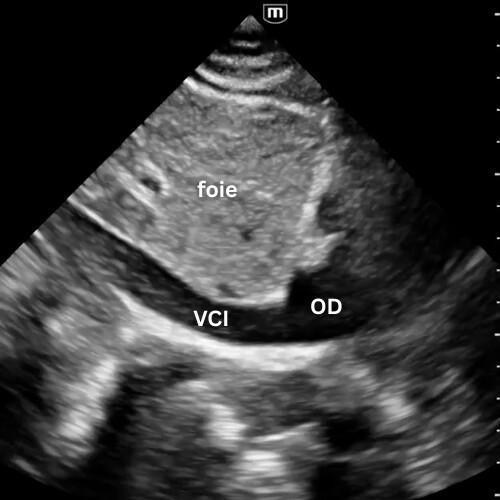

🔹 Veine Cave Inférieure (VCI)

→ Le patient est-il plein ou vide ?

Depuis la fenêtre sous-xiphoïdienne, faites pivoter la sonde en orientant le marqueur vers la tête du patient, légèrement vers son épaule gauche, afin de visualiser la veine cave inférieure à son abouchement dans l’oreillette droite.

Sa taille et sa variabilité respiratoire donnent une idée du remplissage, mais cette approche devient moins fiable devant les autres mesures comme l'evaluation des pressions de remplissage du VG. Ces techniques seront détaillées dans la suite du module cardiaque.

La VCI peut encore dépanner, mais ne doit plus être la boussole du remplissage toute seule.